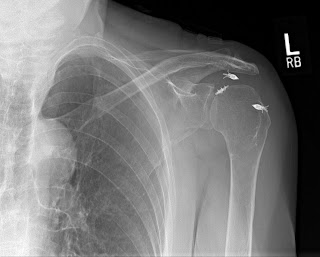

Each patient has had an arthroscopic rotator cuff repair by another surgeon. The first set of films demonstrate that the metal anchors have pulled out of the very soft bone and as a result the tendon has retorn after a rotator cuff repair. This failure was within the first year. This patient was in therapy for many months and could never lift her arm after the repair. Her pain was considerable and she became very unhappy with the situation and eventually came to me for help. A simple x-rays tells the whole story. No MRI needed here. The only set of post operative x-rays done were those done in my office about a year after surgery.

The fact that the anchors are now out of the bone, floating in the joint, indicate that this mechanism of failure. Rotator cuff tendon quality also affects the success of a tendon repair. Poor quality tendon in more likely to retear. Larger tears involving more than one of the 4 rotator cuff tendons will have a higher failure rate as well. Patients over 65 years of age and chronic tendon tears will also have higher rates of failure.

Notice the metal anchors above that seem to be floating in the joint. This foreign body in the joint is very painful. I did surgery on the above patient to remove the anchors arthroscopically. Her pain improved, but her function never recovered. Although I thought she would have done well with a reverse total shoulder replacement, she said that she had enough surgery. I advised her about the limits of surgery under these conditions and, after surgery, she was happy that her pain was improved.